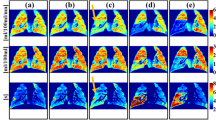

Ventilation

No subject showed ventilation increase (LER-Npost/LER-Npre > 1.06) in any region of interest. The direct radiation response of ventilation biomarkers (at MD point) in all ten pigs showed lower ventilation values post-RT than pre-RT. All five group A WMS and four out of five group B WMS showed ventilation decline (LER-Npost/LER-Npre < 0.94). The remaining group B WMS had LER-Npost/LER-Npre = 0.95 at the MD point. Ventilation decline was not observed in any of the subjects at the CON point. Eight of ten subjects had a low ventilation value (LER-Npost ≤ 1.1) at the MD point and only one was classified as low ventilation in the contralateral lung (CON point). These results demonstrate ventilation decline after treatment in high-dose regions of the ipsilateral lung but not in the unirradiated areas of the contralateral lung. Therefore, CT-ventilation biomarkers demonstrate direct radiation damage via a reduction in ventilation.

Group B WMS had seven additional points of interest evaluated in addition to the direct radiation damage and contralateral control points. These included four points evaluating indirect radiation damage and three selected based on their ventilation values. Changes in ventilation from pre- to post-RT, as quantified by the LER-N ratio, are shown for all nine points of interest from Table 1 for the five group B subjects in Fig. 5. Xs within the box-and-whisker plots denote the mean value for each contour. The left panel shows black patterned boxplots for ventilation-based points of interest (HLV, LLV and HHV as defined in Fig. 4).

Ventilation change (LER-Npost/LER-Npre) at all nine points of interest in group B WMS. LER-Npost/LER-Npre = 1 indicates no change, and LER-Npost/LER-Npre < 0.94 was defined as ventilation decline. The reduced ventilation is most evident at HLV and MD points. Fed points show more ventilation decline than not fed points but are not significantly different (p > 0.12). Acronyms: HLV = High–Low Ventilation, LLV = Low–Low Ventilation, HHV = High–High Ventilation, MD = Maximum Dose, LDF = Low Dose Fed, LDNF = Low Dose Not Fed, NDF = No Dose Fed, NDNF = No Dose Not Fed, CON = Contralateral Control.

HHV points had high ventilation values ranging from 1.25 to 1.48 and did not show pre- to post-RT ventilation decline, with a mean and standard deviation Jacobian ratio values of LER-Npost/LER-Npre = 1.02±0.03. LLV points also did not show any post-treatment ventilation decline (LER-Npost/LER-Npre = 1.00±0.01) and had low ventilation values ranging from 1.02-1.1. HLV points ranged from 1.2–1.27 (pre-RT) to 1.03–1.1 (post-RT), all showing ventilation decline. On average, HLV had LER-Npost/LER-Npre = 0.88±0.03, corresponding to a 12% ventilation decline. The HLV post- to pre-RT LER-N ratio was significantly different than that of the HHV (p = 0.005) and LLV (p = 0.001) points.

The right panel shows all the vessel-centered radiation response points from Fig. 3. The max dose region had a significantly different LER-N ratio than the contralateral lung (0.91 vs. 0.98, p = 0.003). At indirect points of interest, ventilation values were moderate-high pre-RT (range 1.1–1.35) and low-high post-RT (range 1.09–1.25). For all pigs, there was no ventilation decline indicated at either of the ‘Not Fed’ points of interest (NDNF and LDNF). For the ‘Fed’ points, the results were more mixed across subjects; in the low dose region, one WMS (subject C) showed ventilation decline at the LDF point, while three WMS (subjects C–E) showed ventilation decline in the no dose region (NDF). LER-N ratios were not significantly different between fed and not fed contours in the low-dose (0.97 vs. 0.98, p = 0.35) or no-dose (0.94 vs. 1.00, p = 0.12) regions. Indirect radiation-induced damage points of interest are shown in the brown (low dose) and blue (no dose) box plots of Fig. 5. This plot visually demonstrates more ventilation decline in fed contours. This result agrees with previous work by Wallat et al.17 that saw a greater ventilation decline in regions fed by an irradiated airway, but the difference in ventilation was not statistically significant.

To summarize, ventilation biomarkers indicate pre- to post-RT ventilation decline at MD and HLV points and no decline in any subject at CON, HHV, LLV, NDNF, and LDNF points. Ventilation decline is seen in some, but not all, subjects at the LDF and NDF points.